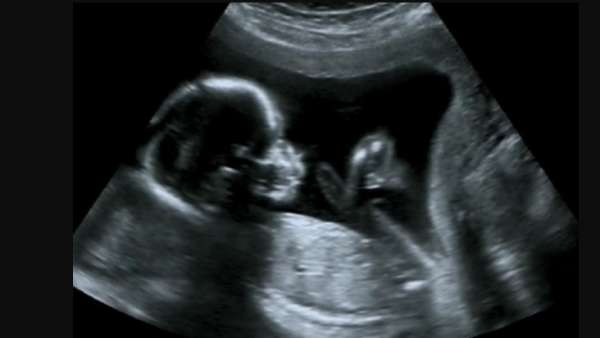

24 வாரங்கள் சென்ற பின்னர் வெறும் 600 கிராம் எடையுடன் ஐந்தரை மாதத்தில் தனியார் மருத்துவமனையில் தம்பதிக்கு குழந்தை பிறந்தது.

அங்கு குழந்தைக்கு நுரையீரலில் அழுத்தம் அதிகமாக இருப்பதால் உடனடியாக சிகிச்சை அளிக்க வேண்டும் என மருத்துவர்கள் கூறியுள்ளனர்.

இதற்காக நைட்ரிக் ஆக்சைடு வாயு மூலம் 4 நாட்கள் வெண்டிலேட்டரிலும் 2 மாதம் ஐசியுவில் குழந்தை வைக்கப்பட்டு தொடர்ந்து சிகிச்சை அளிக்கப்பட்டது.

மருத்துவர்கள் தொடர் முயற்சியின் காரணமாக 600 கிராம் எடையுடன் பிறந்த குழந்தையின் எடை 1.7 கிலோவாக அதிகரித்து உள்ளது.